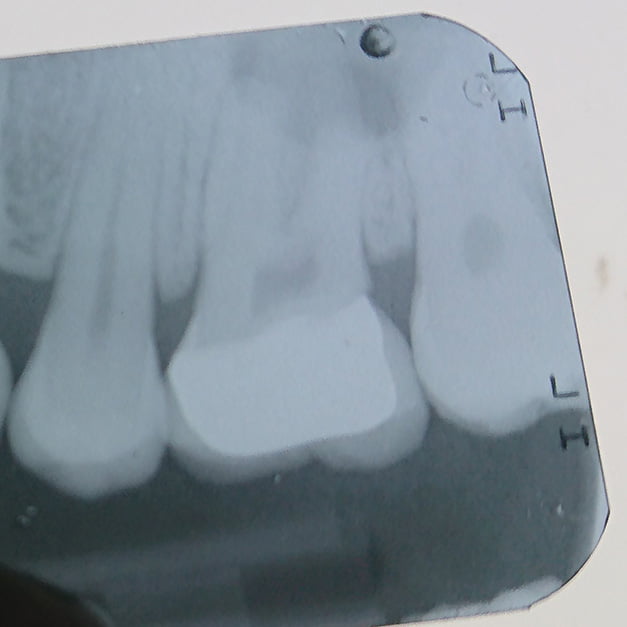

Bitewing

Impacted teeth, carious lesions

periodontal or periapical pathology